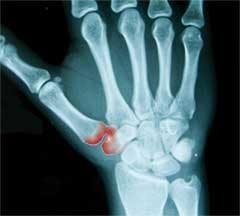

Another observation is that the primary form of arthritis of the base of the thumb is most common in women over 40.3 According to my hand specialist, it is fairly common among long–practicing dental hygienists. The constant pinching action that a hygienist applies at the tips of her fingers transfers up to 10 times its force by the time it reaches the base of the thumb.6 In other words, one pound of pressure applied at the tips of your thumb and forefinger equals 10 pounds of pressure at the base of the thumb. That's a lot of pressure! There's no telling how much pressure we apply during the course of a day's work, often for several minutes up to more than an hour at a time. Imagine a mortar and pestle, grinding herbs or chemicals, and you will have a basic idea of the shape and actions of the bones in the base of the thumb. The constant grinding that occurs when one is gripping a scaler while attacking some hard deposits of calculus day after day is going to take its toll. Gradually, the cartilage that cushions the joint is worn away.3

The most common and early symptom that occurs is pain at the base of the thumb when grasping or pinching an object such as opening a jar or turning a key.5 In our case, instruments are the objects. Also, swelling and tenderness at the base of the thumb can occur.1 Looking back, the first symptom I noticed was a soreness when I would attempt any act of placing my hands on a flat surface while attempting a push–up, the Yoga position such as "downward facing dog," or "the plank" in Pilates. I also noticed weakness in my hands after a particularly tough day of scaling teeth, a day when I am left wondering if anyone flosses his or her teeth! Other times, I would be turning the steering wheel of my car and would get a sharp pain radiating up from my wrist. The symptom that got my attention was soreness in the muscle at the base of my thumb. Thinking that this was a sign that I was wearing the wrong size of surgical gloves, I spent at least two years looking for a better–fitting glove. I tried a cortisone shot, which worked great for about three months, only to have the symptoms return. That's when I finally got an appointment with a hand specialist.

Now here I am again, faced with the inevitability of having to turn away from the security of being able to make a living, save for retirement (which was not supposed to be for another 10 years), and then be able to travel comfortably with my husband when I do retire. Standing there with my doctor looking at my X–rays, he asked me that dreaded question: "Do you plan on retiring soon?" I bravely answered that I wanted to work chairside until I was at least 60. "You're not going to make it," he replied. I felt the ground slip away from under my feet. I was like a child being dropped off at kindergarten on the first day of school, clinging to my mother's skirt. Looking up into her eyes, I was silently begging her not to leave me in this strange, new place. I didn't want to be left there by myself! But pride wouldn't let me show my despair.